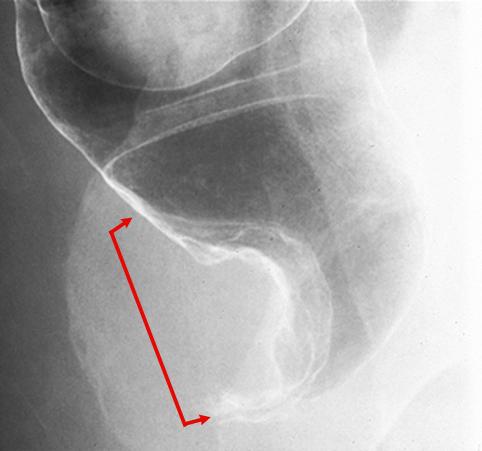

A case of rectal endocrine cell (small cell) carcinoma with a partial adenocarcinoma component.

Malignant epithelial tumor/Undifferentiated carcinoma

Large intestine(Colon)/Rectum

X-ray

Type 1 Protuberant (polypoed) type/

40 -

muscularis propria